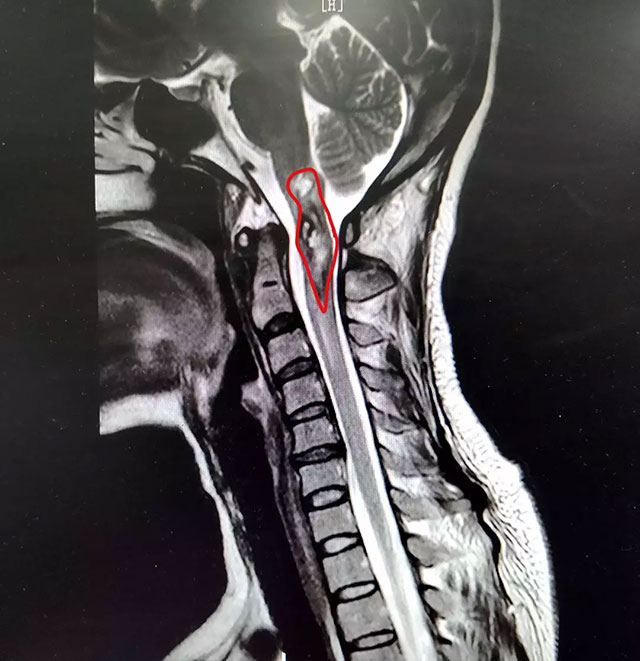

▲ 潘仁龙主任指出患者病灶位置

在患者身体条件允许的情况下,通过对患者进行选择性脊髓血管造影检查,明确诊断其延髓-颈2位置的占位病变为海绵状血管瘤伴脊髓空洞症。

▲ 经过治疗,患者脊髓内出血得到控制